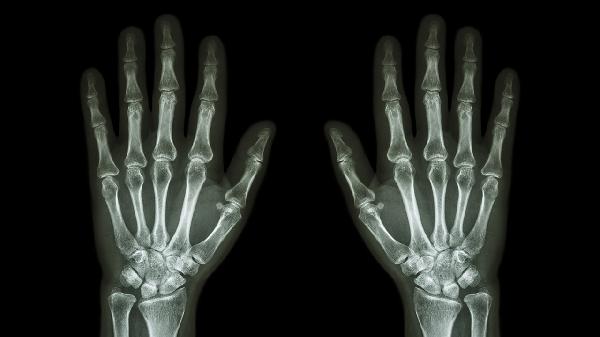

普通骨折多由交通事故、高处坠落等明确外伤导致,骨质结构原本正常,暴力超过骨骼承受极限时发生断裂。骨折线清晰且周围无异常骨改变,常见于四肢长骨如桡骨、胫骨,通常伴随剧烈疼痛、畸形和功能障碍。治疗以复位固定为主,可采用石膏外固定或钛合金接骨板内固定,配合塞来昔布胶囊等药物缓解疼痛,康复期需逐步进行关节活动度训练。